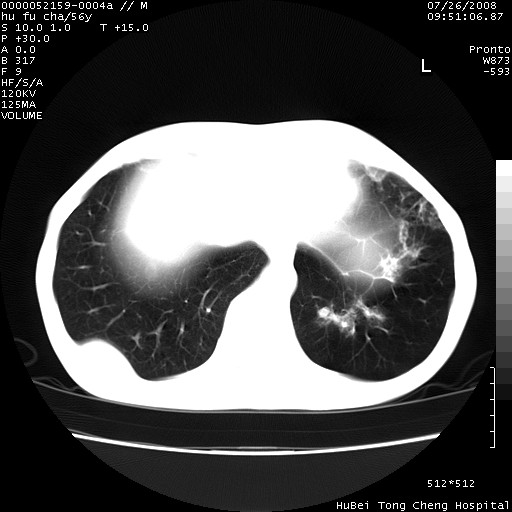

以下是引用zsl6918在2008-8-25 22:47:00的发言:[br]胸骨,胸椎及肋骨均可见多发转移表现,肝内低密度结节不除外转移。原发灶可能在右肺。双侧可见支扩表现。